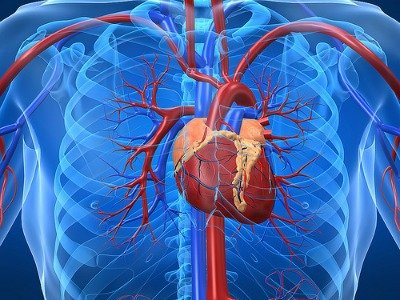

Në qoftë se keni dëgjuar për herë të parë për kancerin e zemrës, nuk jeni të vetmit për shkak se rastet e kancerit të zemrës me të vërtetë janë të rralla. Zemra është një muskul i cili për nga natyra nuk përmban yndyrë. Toksinat nga pjesët e afërta mund t’i modifikojnë gjenet tona, gjë që ndonjëherë rezulton në zhvillimin e qelizave të kancerit.

Kanceri i zemrës (tumori primar i zemrës) është kancer që shfaqet në zemër. Tumoret kancerogjene (malinje) të cilat zhvillohen në zonën e zemrës janë shpesh sarkoma të indeve të buta, dhe shumica e rasteve të tumorit kardiak janë beninje, transmeton koha.net.

Letër lexuesit — pse po kërkojmë mbështetjen tuaj KontribuoShumica e rasteve të kancerit të zemrës janë në fakt pasojë e përhapjes së qelizave të kancerit nga organet e tjera, më së shpeshti nga zona e mushkërive, mëlçisë dhe lukthit. Edhe pse kanceri i zemrës është i rrallë, ai është gjithsesi i mundur. Sa për parandalimin e kancerit të zemrës, ky parandalim është në fakt shumë i ngjashëm me parandalimin e të gjitha formave të tjera të kancerit.